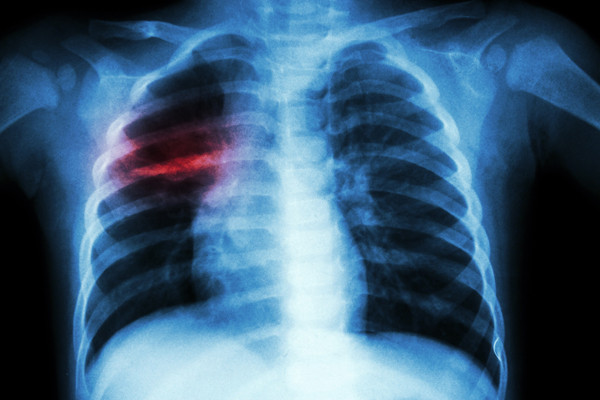

Theo Phó Giáo sư - Tiến sĩ - Bác sĩ Cao Hữu Nghĩa (Viện Pasteur TP. Hồ Chí Minh), thủy đậu vốn là một bệnh lành tính nhưng nếu không được phát hiện sớm để điều trị kịp thời và đúng cách có thể gây nhiều biến chứng nguy hiểm. “Mụn nước do thủy đậu có thể gây viêm da “bội nhiễm”, để lại các vết sẹo lõm trên da về sau. Biến chứng thứ hai có thể gặp phải là viêm phổi với triệu chứng như đau ngực, khó thở, tím tái, ho ra máu. Nguy hiểm hơn, bệnh có thể dẫn đến viêm não, rối loạn tâm thần, co giật, hôn mê…, thậm chí tử vong” - BS Nghĩa cho biết.

Một trường hợp bị biến chứng viêm phổi do thủy đậu